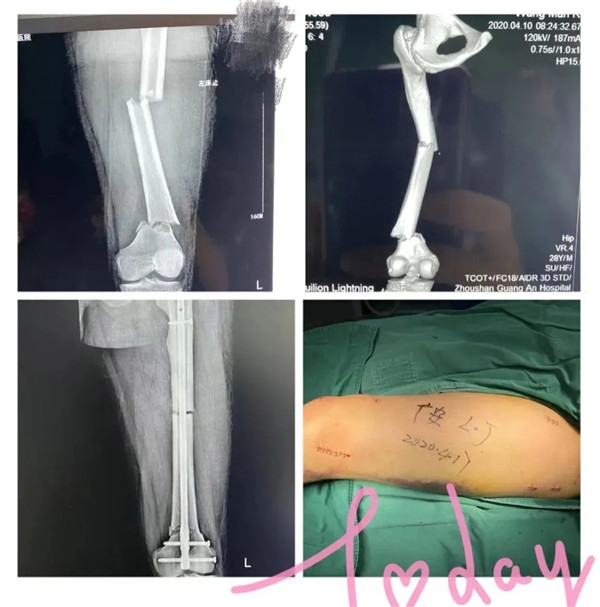

受傷的是家住城北的年輕小伙小王,早上騎電動(dòng)車去上班速度太快而不慎摔傷。急診醫(yī)生初步檢查,判斷是大腿骨骨折,立即予以拍片檢查。結(jié)果顯示:左股骨多段粉碎性骨折。小王左腿股骨竟斷成三截 !須做手術(shù)治療。病人和家屬看到片子后,都有點(diǎn)嚇傻了,急得語無倫次,不斷地追問醫(yī)生:“醫(yī)生,這該怎么辦呢?骨頭都斷這樣了,還能接好嗎?……”醫(yī)生趕緊安撫病人和家屬:“到了我們醫(yī)院,您們放心好了。等檢查完善后,我們會(huì)盡快施行手術(shù)治療的”。小王當(dāng)即辦理了住院手續(xù)。

4月17日,在經(jīng)過周密的術(shù)前準(zhǔn)備,小王的身體狀況符合手術(shù)指征,并征得家屬同意后,廣安骨科中心副主任羅軍帶領(lǐng)團(tuán)隊(duì)為他實(shí)施了閉合復(fù)位磁力導(dǎo)航髓內(nèi)釘內(nèi)固定微創(chuàng)手術(shù)。

手術(shù)在腰部麻醉下進(jìn)行,術(shù)中僅需幾個(gè)微創(chuàng)小切口,創(chuàng)傷小,出血少,一個(gè)小時(shí)后,手術(shù)順利完成。術(shù)后患者病情很快恢復(fù),生命體征平穩(wěn)。第二天,小王就可以拄拐下地活動(dòng)并進(jìn)行康復(fù)鍛煉。日前,在醫(yī)護(hù)團(tuán)隊(duì)的精心照料下,他已出院回家休養(yǎng)。出院前,小王對(duì)著醫(yī)護(hù)人員豎起了大拇指:“廣安醫(yī)院的醫(yī)生技術(shù)好、態(tài)度佳,真牛!”

據(jù)介紹,此次為小王實(shí)施的磁力導(dǎo)航髓內(nèi)釘內(nèi)固定手術(shù)以交鎖髓內(nèi)釘技術(shù)為基礎(chǔ),以新興的磁力導(dǎo)航技術(shù)為依托,以微創(chuàng)為特點(diǎn)。相比傳統(tǒng)手術(shù),定位更加準(zhǔn)確,具有減少手術(shù)時(shí)間、減少手術(shù)出血和創(chuàng)傷、減少術(shù)中放射次數(shù),且術(shù)后恢復(fù)快,傷口小,基本不留明顯疤痕的優(yōu)點(diǎn),在磁力導(dǎo)航下,實(shí)現(xiàn)骨折部位的精準(zhǔn)復(fù)位?;颊咝g(shù)后僅一天就可以開始扶拐下地活動(dòng)并進(jìn)行康復(fù)鍛煉。